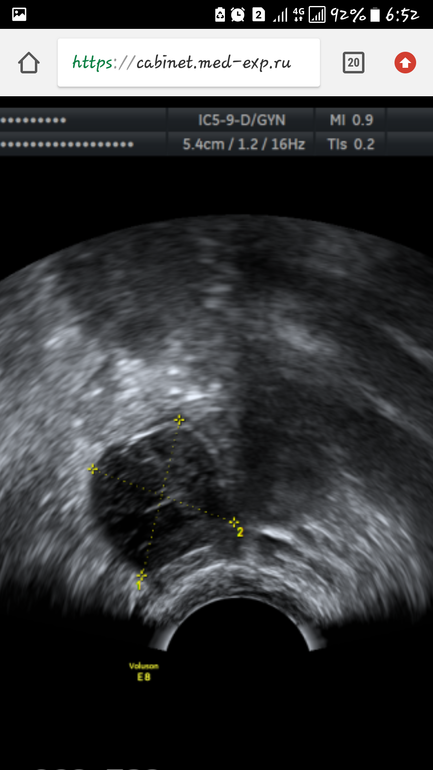

А заключения письменного нету? Только снимки? Ну лично я вижу замеры плодного яйца вроде как. Еще желточный мешочек.

Я вижу измерения пя в матке.почему вб?есть подозрения?

Да.мне сказали в яичнике 2 жт. И в трубе что то непонятное не поймут что пока

Я так понимаю что подозрение на второе пя.такое вполне возможно.толтко ждать.но одно пя у вас точно в матке